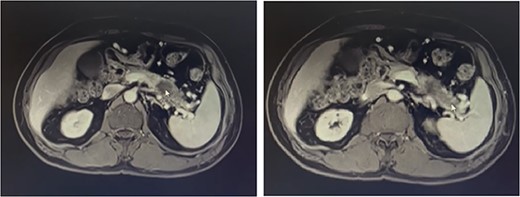

Our patient is a 55-year-old man with a history of rectal adenocarcinoma cancer in the last 2 years. At that time, he presented with flank pain and kidney stones. After examination and diagnostic tests, he was diagnosed with colon cancer that a 12 cm mass was reported and then colectomy surgery was performed. Then six sessions of radiotherapy were considered for him. In the new regression, 2 years after the colectomy surgery, during the examination phase, due to the exacerbation of pain, a computed tomogaphy (CT) scan (Figs 1 and 2) and endoscopy were requested for the patient, in which pancreatic cancer was observed. After that, the patient was placed under endoscopic ultrasound (EUS), which is reported. There was one 35 × 29 mm hypoechoic and round lesion with ill-defined border in pancreatic tail with no involvement of pancreatic duct or splenic vessels in favor of metastasis. EUS fine-needle biopsy with needle 22G was performed. Then the patient underwent a biopsy and the final confirmation was made.

Metastatic masses can be seen in the pancreatic tissue on the CT-Scan (transverse/axial view)